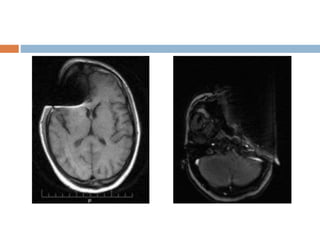

RF overflow/Shading artifact

 Non uniform, washed out appearance in an

image.

 Occurs when the signal received from the patient

is too intense to be digitized by analog to digital

converter.

 Auto prescanning usually adjusts the receiver

gain.

 Post processing methods also existing but may

be time consuming.

RF overflow/Shading artifact Non uniform, washed out appearance in an image.  Occurs when the signal received from the patient is too intense to be digitized by analog to digital converter.  Auto prescanning usually adjusts the receiver gain.  Post processing methods also existing but may be time consuming.